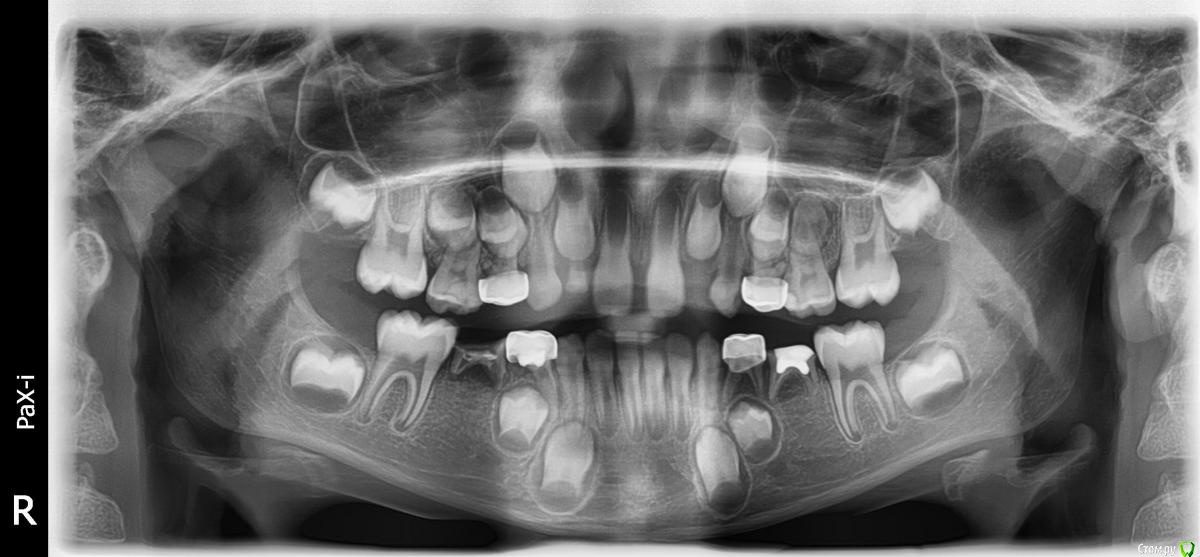

Mikhail_29_rus Опубликовано 6 сентября, 2016 Поделиться Опубликовано 6 сентября, 2016 Фиксация коронки на зубе 64 у этого же ребенка - тоже моих рук дело. Работа с зубом 64 прошла без осложнений со стороны пародонта и также функционирует по сей день.Вот как выглядит ситуация на ОПТГ почти через 3 года с вышеописанным кейсом с 3M коронками (сюрпризом стали выявленные адентии 35,45 зубов) Ссылка на комментарий